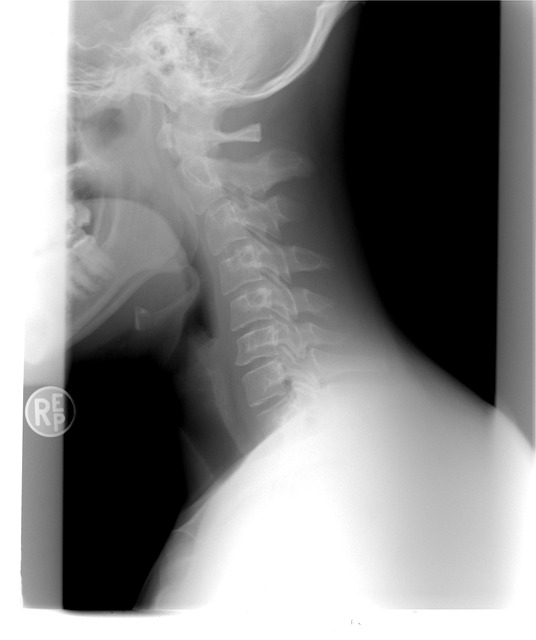

Skolióza páteře

Je opravdu hodně smutné, pokud vás bolí záda, já tohle moc dobře znám. Nejsem už nejmladší, ale také nejsem samozřejmě nejstarší, ale řeknu vám, že někdy ta bolest zad je opravdu hrozná. Někdy ta bolest zad je opravdu neúnosná. Mám bohužel skoliózu páteře, skoliózu, páteře mi zjistili, když mi bylo sedmnáct let. Ještě jsem nebyla ani plnoletá a už jsem měla problémy se zády. Moje maminka tomu nemohla stále uvěřit a stále dokola se ptala pana lékaře. Jestli se třeba nespletl, že já rozhodně nemůžu mít skoliózu páteře, maminka si to myslela, protože jsem závodně dělala aerobik a také jsem plavala a říkala si, že rozhodně nemůžu mít žádné zdravotní problémy a už vůbec ne skoliózu páteře.